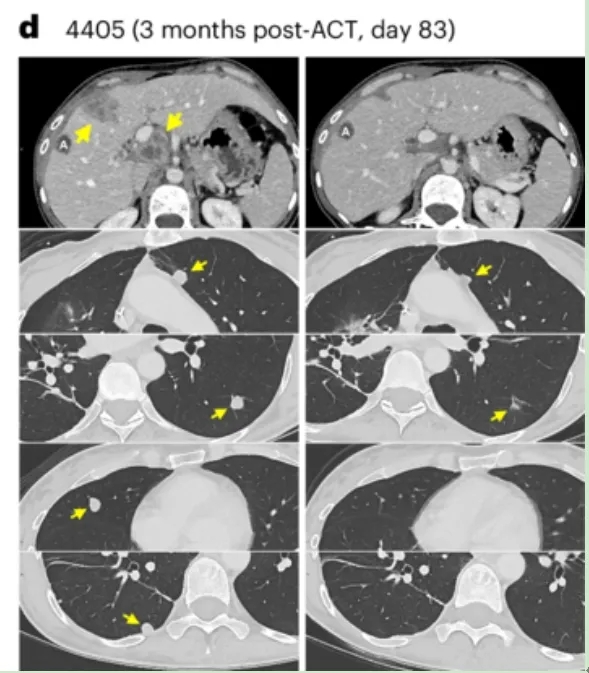

结果显示:根据RECIST标准,42.8%患者(3例)达到临床客观缓解,肺、肝脏、淋巴结等转移灶消退,缓解持续时间4~7个月。

值得一提的是,其中患者4405(转移性直肠癌)在TCR-T细胞回输后,影像学检查显示其肝转移、门静脉淋巴结及多发肺转移病灶均完全消退(详见下图)。